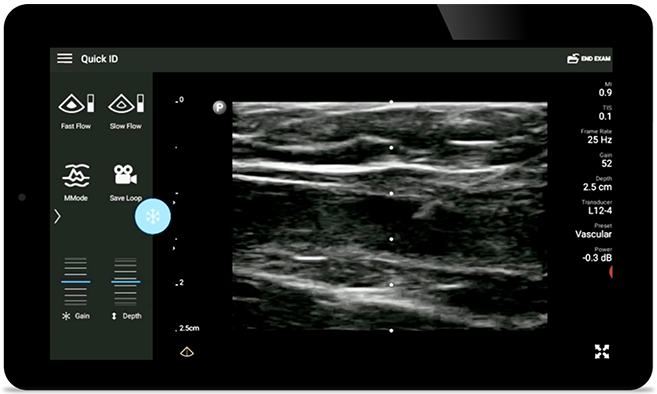

Real-time ultrasound guidance can improve the accuracy and safety of CVC insertions.

• 12 to 4 MHz extended operating frequency range • Aperture size: 34mm • 2D, steerable color Doppler, M-mode, advanced XRES and multivariate harmonic imaging, SonoCT • High resolution imaging for shallow applications: soft tissue, vascular, superficial, musculoskeletal, and lung • Center line marker • USB-C transducer with replaceable cable